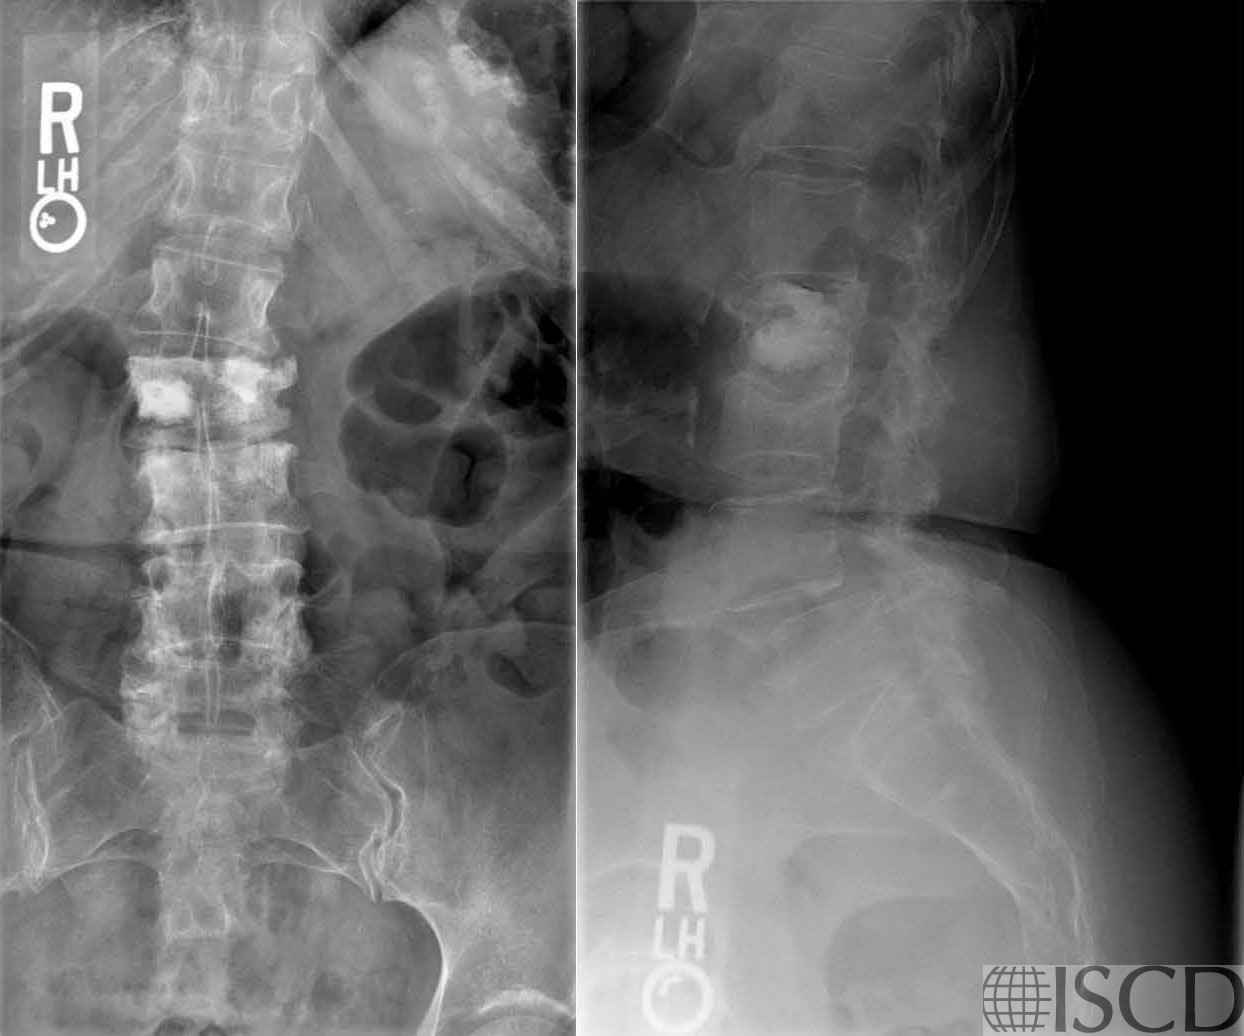

There is a kyphoplasty at L2 on the Hologic lumbar spine scan. This level would be omitted from analysis. Because there is also compression at L3, L3 would correctly be removed from analysis. There are bra fasteners visible outside the region of interest.

The accompanying radiographs show the kyphoplasty. There is also compression at L3 and therefore L3 should also be removed from analysis.

These images show vertebral augmentation.